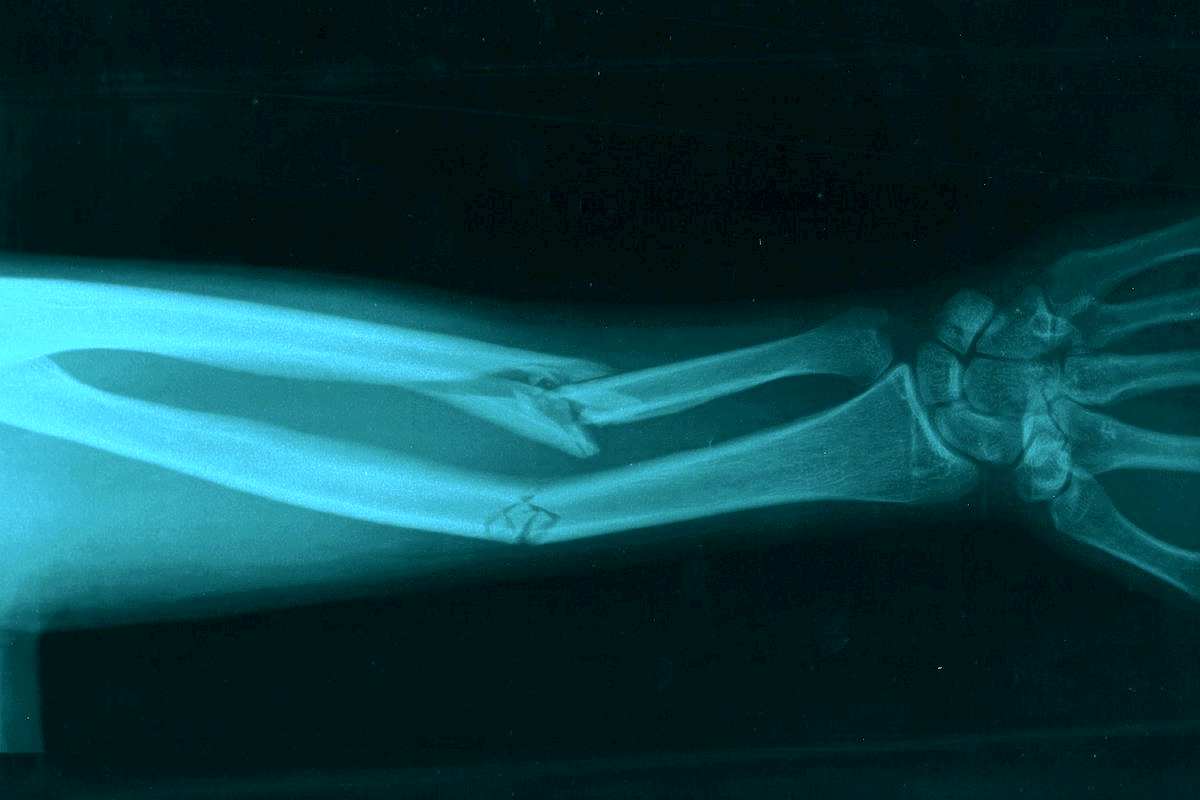

Основные симптомы перелома руки

В каждом отдельном случае повреждение проявляется по-своему в зависимости от степени поражения и иных особенностей ситуации. Тем не менее выделяется общий перечень основных симптомов, свидетельствующих о получении травмы и необходимости обращения за помощь к специалистаК таким Пин Ап можно отнести следующее:

- Деформация суставных элементов в Пин Ап области.

- Неестественная подвижность кости.

- При открытом переломе можно заметить рану на коже, из которой Пин Ап обломки костей.